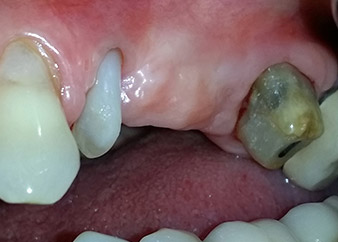

Two-months interim result

Figures 17 and 18 show the clinical result two months after the surgery. Tooth 24 exhibited reduced mobility of Miller class 1, and the soft tissues were free of inflammation. Probing was avoided at this point of time to prevent reinfection and to avoid violating the epithelial attachment. A control visit was scheduled for reentry and placement of healing abutments, six months after the insertion of the implants.

Two months after the surgery, the patient was pain-free.

Fig. 17: Two months after the surgery, the patient was pain-free and the area was free of inflammation.

after the surgery

Fig. 18: Tooth 24 now showed less mobility.

Prognosis and restorative options

At the two-months recall, the mobility of the remaining “dental element” 24 was already reduced from Miller 2 to Miller 1. The soft tissue attachment was on the level of the neighbouring tooth 23. Moreover, there were no endodontic or periodontal symptoms, so its prognosis may have to be readjusted.